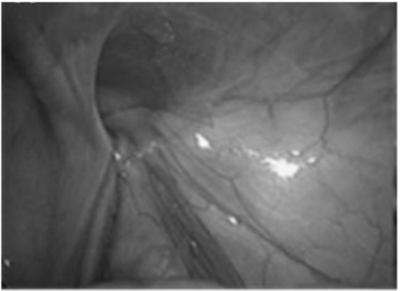

A figura abaixo ilustra a visão laparoscópica intraperitoneal da região inguinal direita de um paciente de 17 anos diagnosticado com hérnia inguinal. Na figura podemos identificar o ducto deferente, vasos espermáticos e vasos epigástricos inferiores, além do defeito herniário. Assinale a principal hipótese diagnóstica.